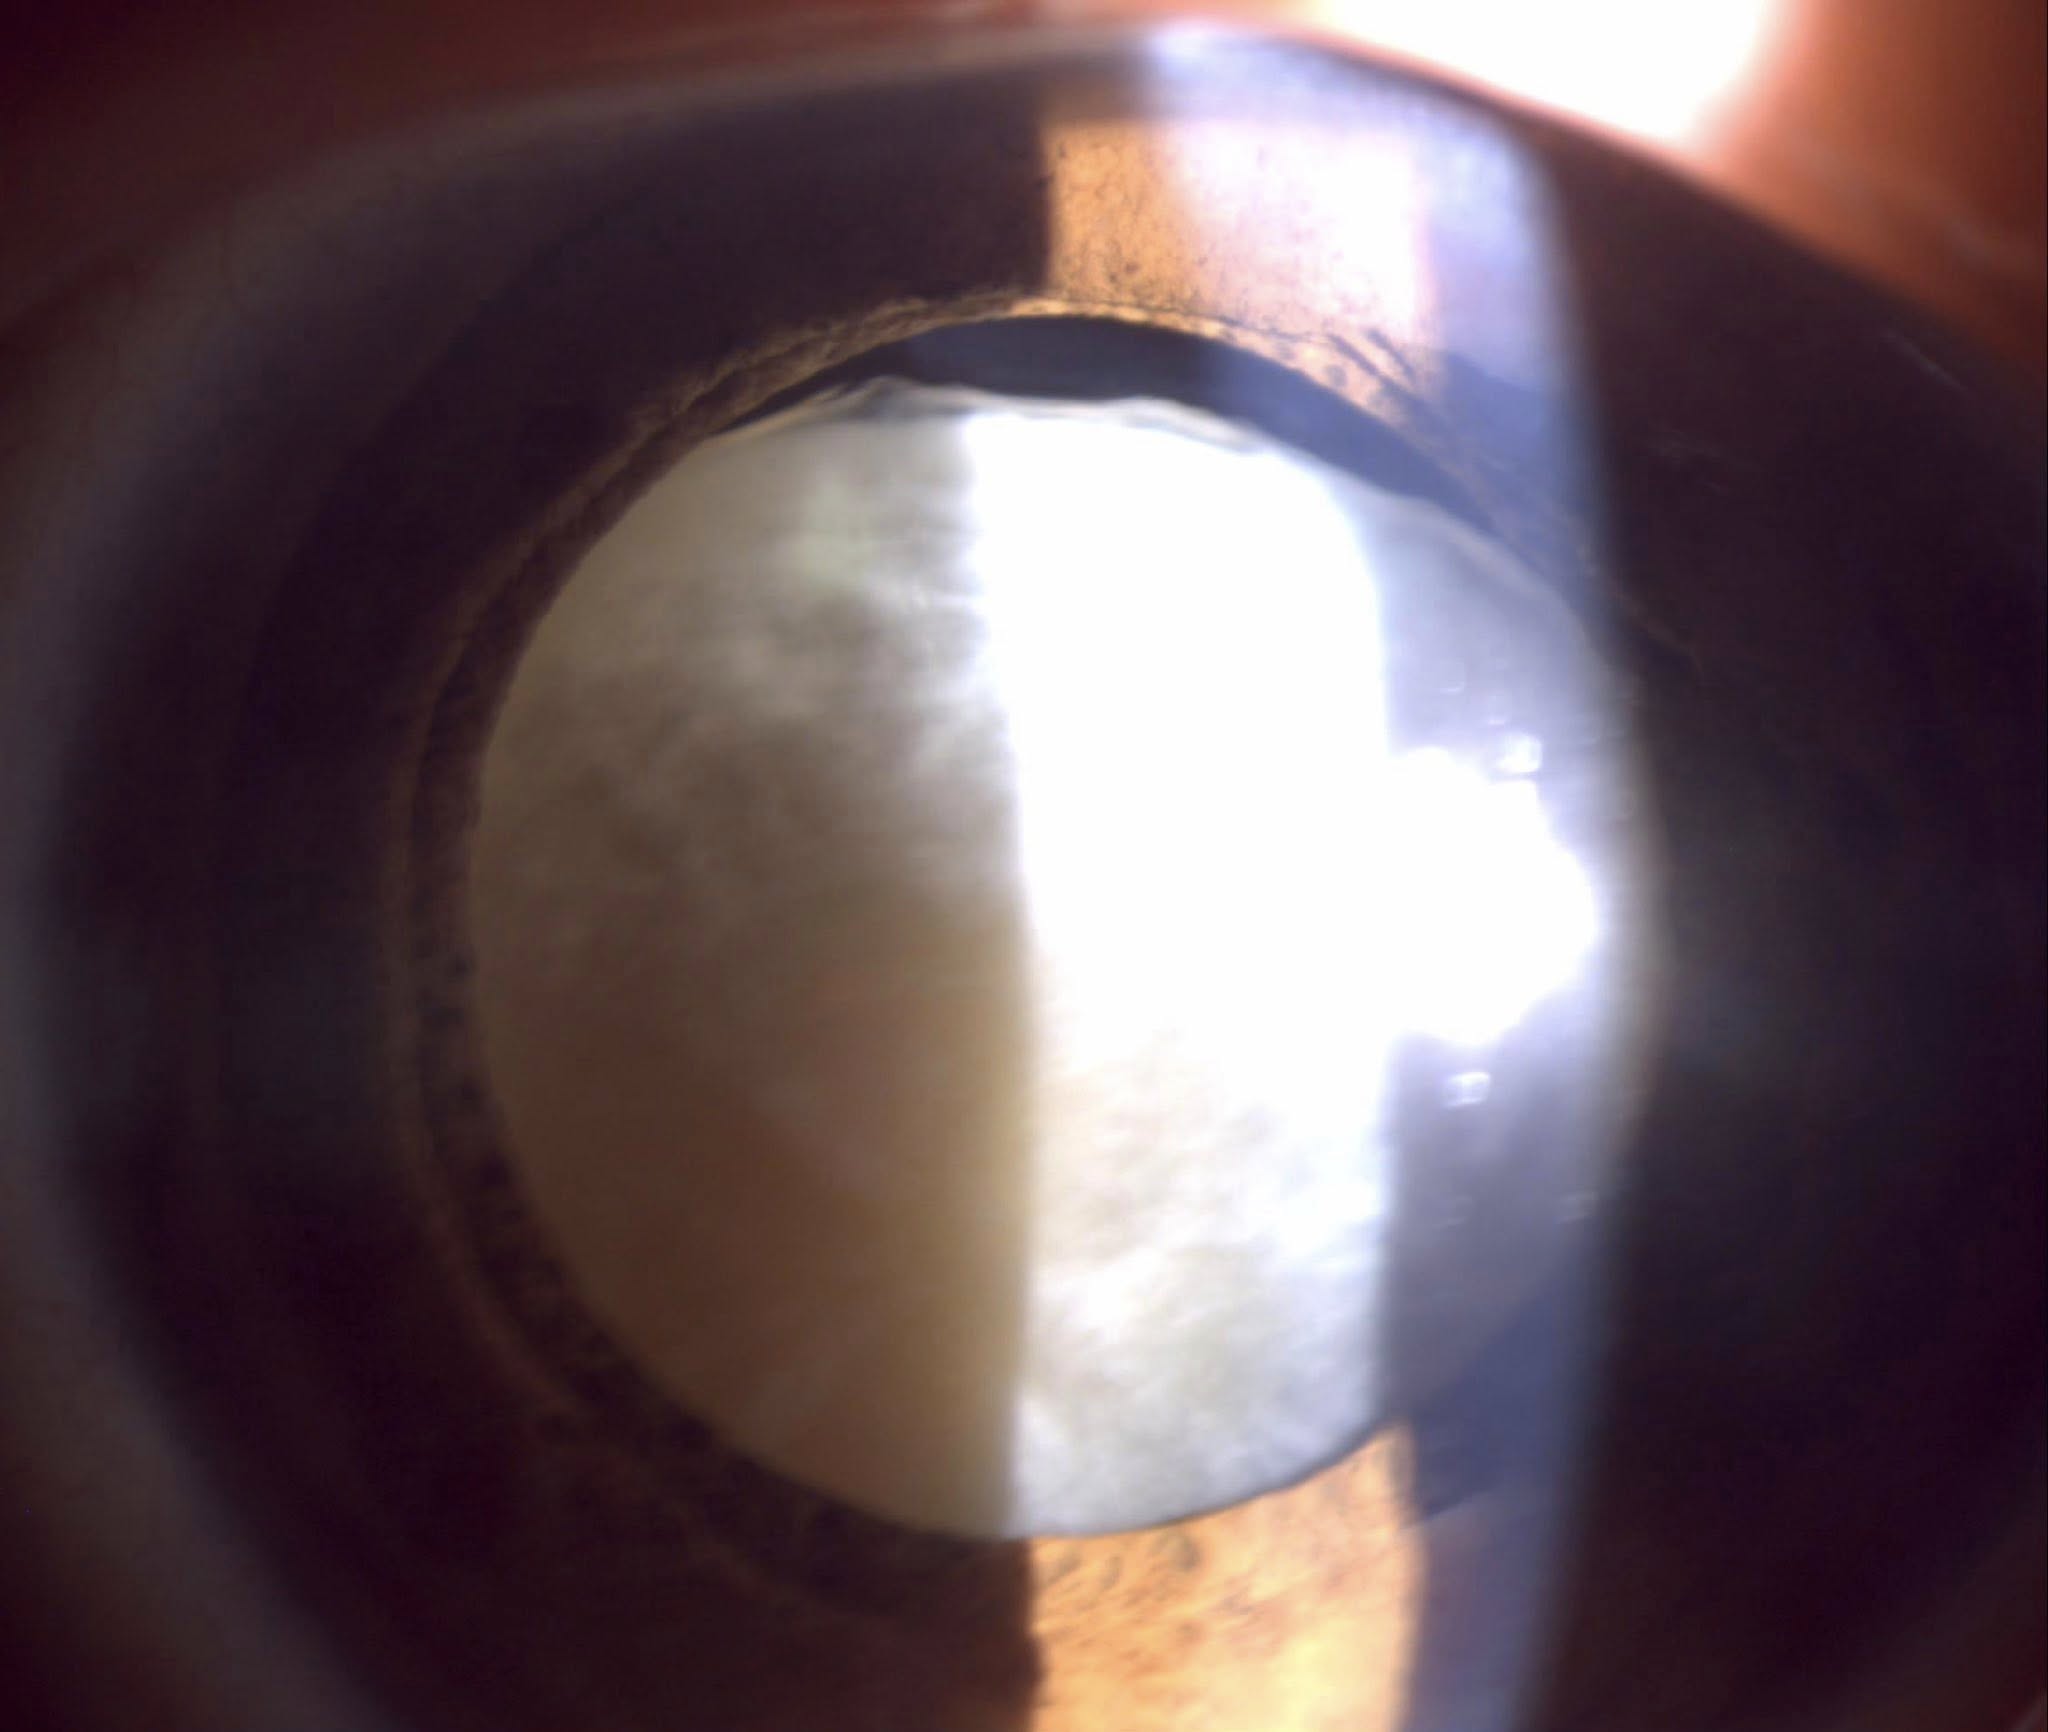

Cazul prezentat aici, deși pentru dr. Ozana Moraru nu a fost unul foarte deosebit, a fost, în schimb, pentru tinerii colegi, specialiști sau rezidenți, care au asistat la operație și, cu siguranță, a fost și pentru pacientă, victimă a violenței domestice, complet nevăzătoare din cauza traumatismelor repetate în zona feței și a ochilor, care au dus la cataractă hipermatură cu subluxație dein cristal la ambii ochi, unul fiind definitiv pierdut, prin glaucom secundar absolut. Legat de tinerii medici observatori, au avut ocazia să vadă o tehnică chirurgicală mai rar efectuată în zilele noastre, fiind mai veche, dar mereu actuală în aceste situații: tehnica intra-capsulară, prin care cristalinul opac și deplasat este extras “în bloc”, pe o incizie de 7-8 mm, care necesită a fi “cusută”, iar cristalinul artificial este unul special, adaptat lipsei de suport, trebuind prins prin diverse tehnici, fie la peretele ocular, fie la iris.

Fotografiile ochiului de azi, din prima zi postoperator (ultimele patru foto), arătau excelent, cu corneea fără pic de edem și cristalinul artificial perfect centrat și, mai mult decît atât, după consultație, stând în sala de așteptare fără pansament, pacienta se uita la televizorul din sală și comenta cu fiica ei ceea ce vedea acolo!